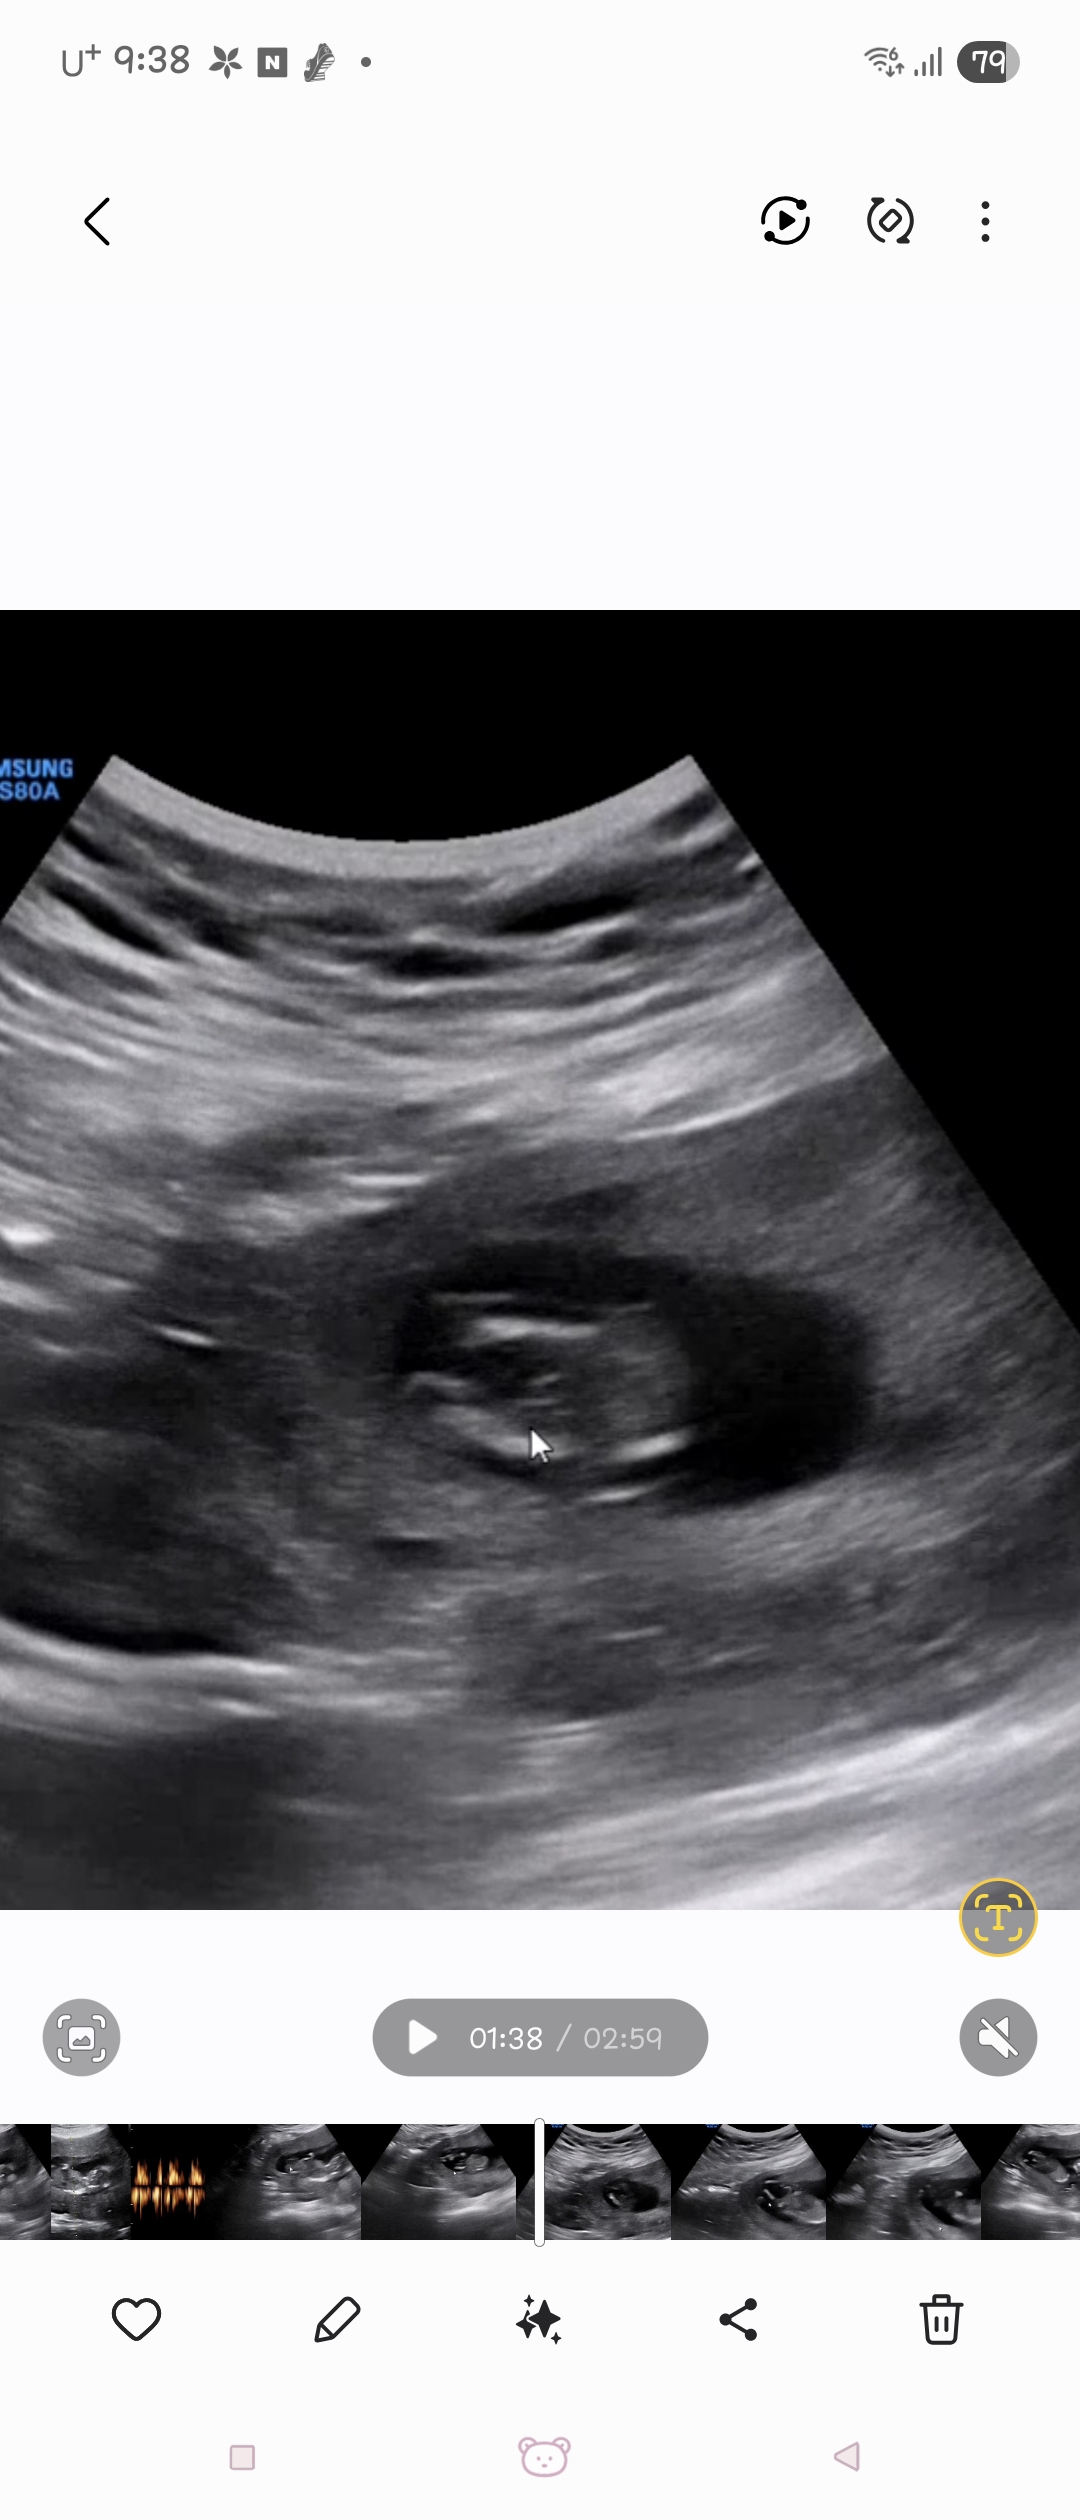

아둘맘 셋째 성별봐주세요...ㅎㅎ

셋째입니다ㅠㅠ 13주4일이에요 아들일까요?

아직 생식기가 안들어가서 저렇게보일 수 있어요!! 각도법이 더 정확할거같아오!

가운데 먼가 보이는거같긴 하네여..! 제 첫째가 딸인데 촘파 볼때 매끈했거든요 ㅠ